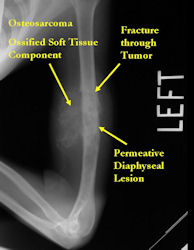

Radiographic Presentation: Conventional Osteosarcoma

There are 3 radiographic presentations for osteosarcomas, depending upon the amount of osteoid/ossification and calcium deposition:

- Mixed sclerotic and lytic, permeative lesion most common radiographic presentation

- Purely osteoblastic, permeative lesion: dense sclerosis and osteoid production

- Purely lytic, permeative lesion: little osteoid production and/or minimal calcium deposition in osteoid

Conventional osteosarcomas are permeative lesions on plain radiographs (borders of the lesion cannot be clearly delineated)

- Wide zone of transition from lytic/sclerotic areas of tumor to normal bone

- Makes borders of lesion hard to define

- Most (90%) arise from the metaphysis of the bone

- Rarely (10%) arise from the diaphysis

- Most conventional osteosarcomas (90-95%) extend through the bone into the soft tissues and form a soft tissue mass outside of the bone